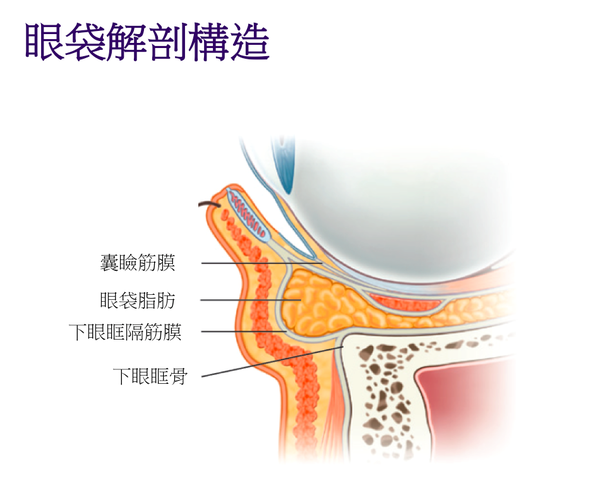

很多人因為勞累過度、熬夜、情緒煩躁、年齡增長等,漸漸地,眼睛周圍的皮下脂肪變得愈薄,眼部肌底血管的血流速度過於緩慢,形成滯流,阻礙氣血運行,導致組織供氧不足,血管中代謝積累過多,該處筋肉色素沉著、鬆弛無力、浮腫,就會導致眼袋、黑眼圈等情況出現!所以常說,必須調理肌底,提升自體修護力,才能喚回緊緻白皙、水潤光滑、有彈性的肌膚!

《黃帝內經》指出,「諸濕腫滿,脾氣散精,上歸於肺,通調水道,下屬膀胱,水精四布,五經並行。」簡單來說,就是水濕浸漬堆積於眼部肌膚,導致眼瞼尤其是下眼瞼因充水而浮腫,眼袋就出現了。